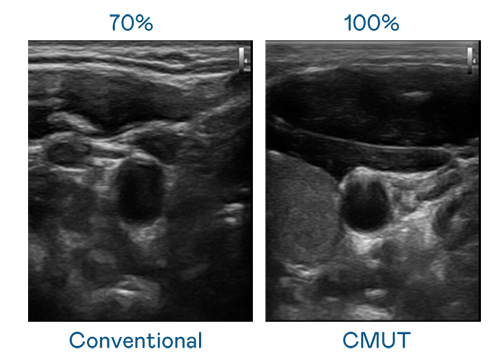

CMUT 技术是一种用电容式微机电元件来产生超音波讯号的技术。与传统 PZT 压电式技术相比,CMUT 频宽增加 30%,更宽频的超音波讯号让影像解析度大幅提升,是实现高影像品质医疗超音波扫描、促进精准医疗发展的关键技术。

超音波影像的解析度高低,首先取决于探头能发出的讯号频宽。酷游官网 CMUT 可提供高清晰的超音波讯号,提供高频宽、高灵敏度、影像纹理细节更高的超音波影像,协助医护人员缩短影像判读时间及利用精准的医疗影像进行诊断。